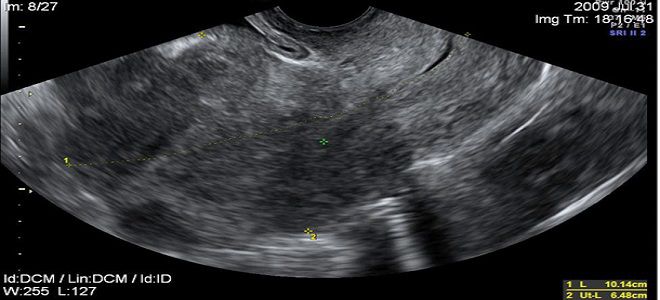

Перед тем как установить диагноз эндометриоза матки, медицинские специалисты проводят ряд исследований. Основным методом диагностики данного заболевания является ультразвуковое исследование (УЗИ). Во время процедуры врачи обращают внимание на следующие характеристики, указывающие на эндометриоз:

- анэхогенные образования диаметром до 6 мм;

- области с повышенной эхогенностью;

- увеличение размеров матки;

- наличие полостей с жидкостью и узлов неправильной формы.

Тем не менее, при наличии воспалительных или инфекционных процессов может произойти повреждение защитного слоя. В результате этого клетки эндометрия проникают в мышечный слой во время очередных циклических изменений, формируя очаг воспаления. При ультразвуковом обследовании врач может заметить характерные изменения, которые отличаются от нормальной структуры мышечной ткани – эндометриоз матки, симптомы и методы его лечения будут рассмотрены ниже.